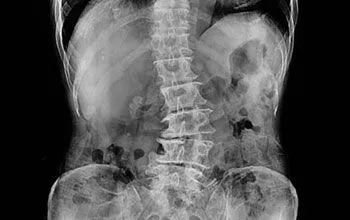

Scoliosis is a medical condition where the spine curves abnormally to the side, often resembling an “S” or “C” shape. This curvature can lead to discomfort, pain, and limited mobility if left untreated. Scoliosis is most commonly diagnosed in children and adolescents, but adults can also develop scoliosis, especially due to degenerative changes in the spine. At Aldridge Family ChiropracticDr. Mark Aldridge, board certified by the National Board of Chiropractic Examiners, provides non-invasive scoliosis treatments aimed at managing pain, improving posture, and enhancing spinal alignment.